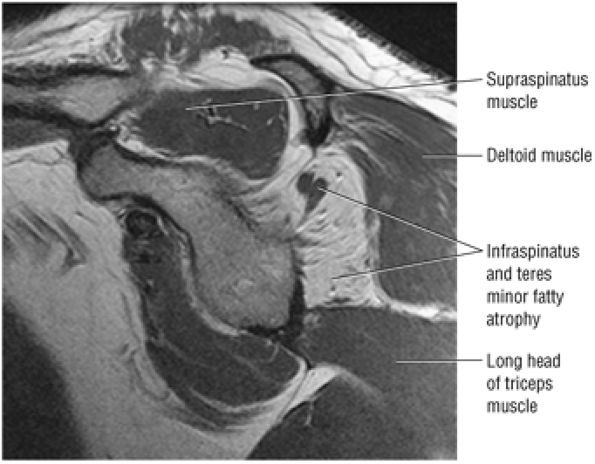

FIGURE 8.15 Infraspinatus ● The infraspinatus functions with the teres minor to externally rotate and extend the humerus. The infraspinatus is more active with the arm in the adducted position and accounts for up to 60% of external rotation force. The infraspinatus contributes to the humeral head depressor action of the rotator cuff.